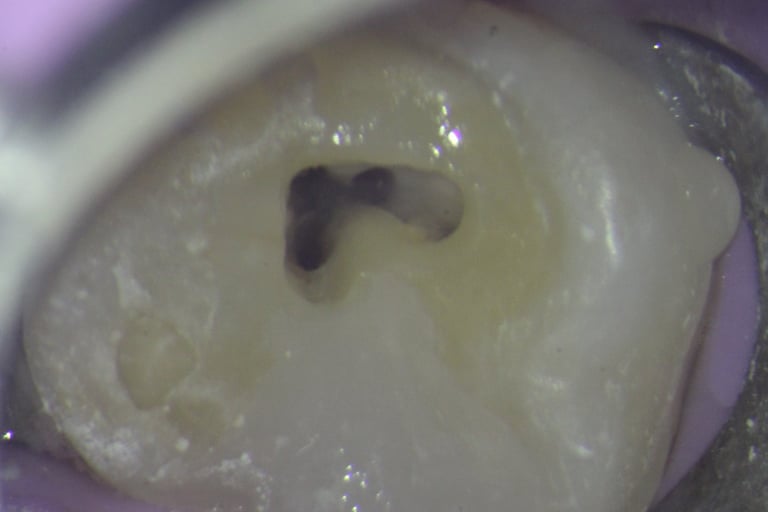

Root Canal Treatment

Precise treatment using advanced microscope technology. Our clinic is enabled in Single sitting RCT as well as 2 sitting RCT.